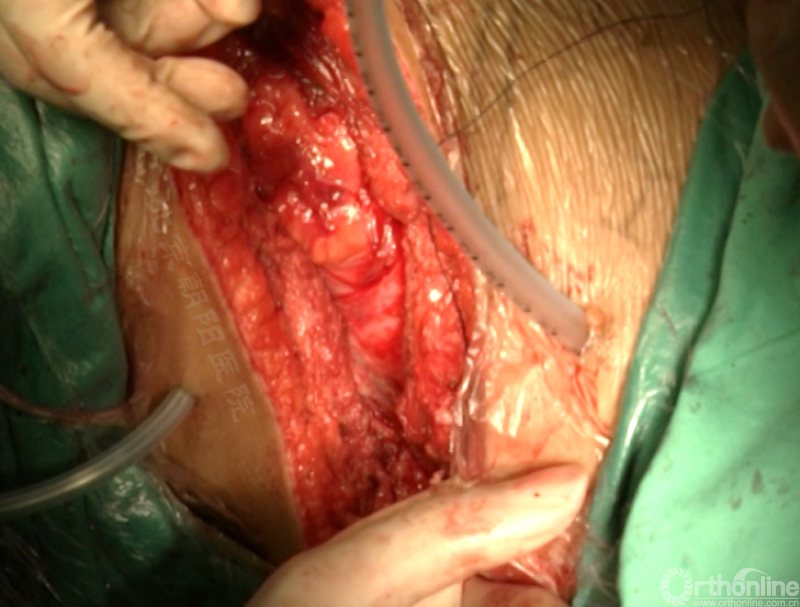

尽量多的闭合胸膜,紧密缝合横膈。

分别缝合第11、12肋骨的骨膜。

留置合适直径的胸腔闭式引流管,根据术中情况选择是否放入腹腔引流。逐层缝合腹壁,逐层缝合皮下组织和皮肤。